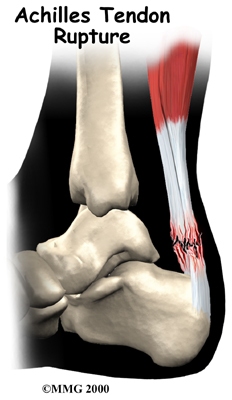

Achilles Tendon Rupture

In severe cases, the force of a violent strain may even rupture the tendon. The classic example is a middle-aged tennis player or weekend warrior who places too much stress on the tendon and experiences a tearing of the tendon. In some instances, the rupture may be preceded by a period of tendonitis, which renders the tendon weaker than normal.

An Achilles tendon rupture is usually an unmistakable event. Some bystanders may report actually hearing the snap, and the victim of a rupture usually describes a sensation similar to being violently kicked in the calf. Following rupture the calf may swell, and the injured person usually can't rise on his toes.

Nonsurgical treatment for an Achilles tendon rupture is somewhat controversial. It is clear that treatment with a cast will allow the vast majority of tendon ruptures to heal, but the incidence of rerupture is increased in those patients treated with casting for eight weeks when compared with those undergoing surgery. In addition, the strength of the healed tendon is significantly less in patients who choose cast treatment. For these reasons, many orthopedists feel that Achilles tendon ruptures in younger active patients should be surgically repaired.

Nonsurgical treatment might be considered for the aging adult who has an inactive lifestyle. This allows the patient to heal while avoiding the potential complications of surgery. The patient's foot and ankle are placed in a cast for aprroximately eight weeks. Casting the leg with the foot pointing downward brings the torn ends of the Achilles tendon together and holds them until scar tissue joins the damaged ends. During this time, your physical therapist will instruct you in safe and proper crutch utilization. After your cast is removed, our physical therapist can have your fitted with a large heel lift to wear for apprximately another six to eight weeks after the cast is taken off.

Surgery may also be suggested if you have a ruptured Achilles tendon. Reattaching the two ends of the tendon repairs the torn Achilles tendon. This procedure is usually done through an incision on the back of the ankle near the Achilles tendon. Numerous procedures have been developed to repair the tendon, but most involve sewing the two ends of the tendon together in some fashion. Some repair techniques have been developed to minimize the size of the incision.